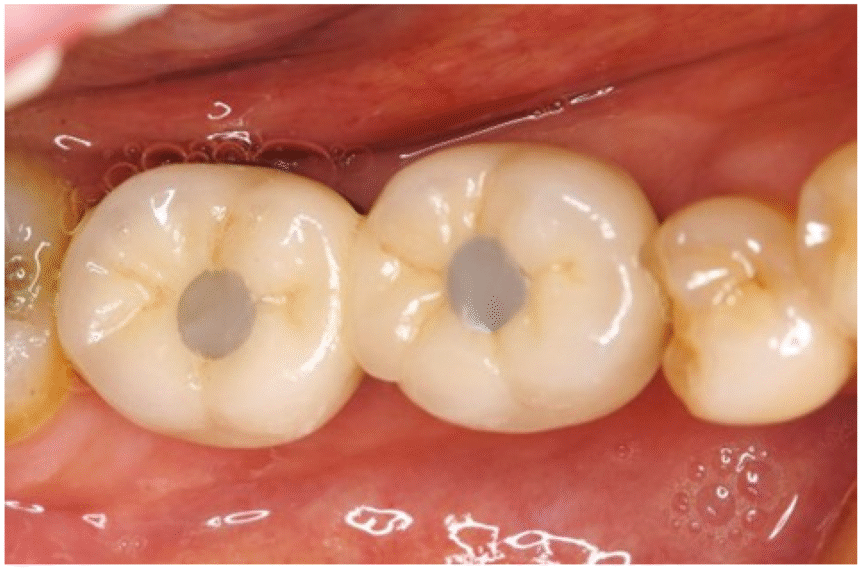

1. Dental Fillings

The most common Teeth Hole Repair method for small to medium-sized cavities, dental fillings involve removing decayed tissue and restoring the tooth with a suitable filling material.

Materials Used:

- Amalgam: Durable and cost-effective, but less aesthetically pleasing due to its metallic appearance.

- Composite Resin: Tooth-colored, aesthetically appealing, and suitable for visible areas.

- Gold: Highly durable, but more expensive and mainly used in specific cases.

- Ceramic: Tooth-colored and resistant to staining, often used in inlays and onlays.